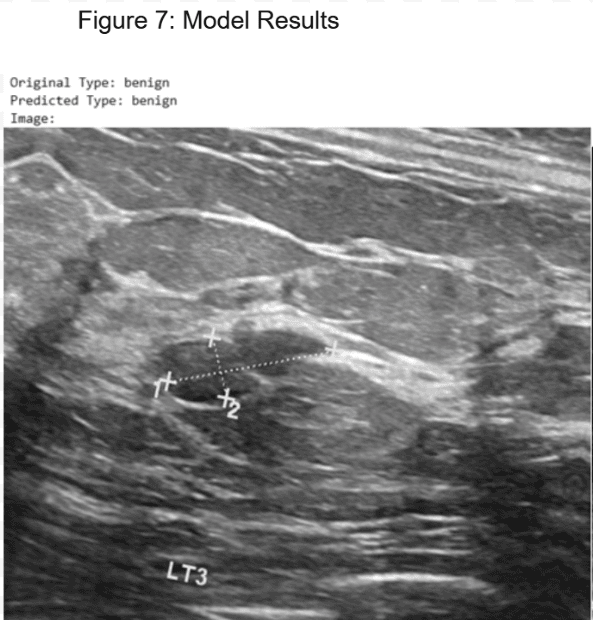

Implementation of deep learning models achieving high accuracy for classification and segmentation using ultrasound images.